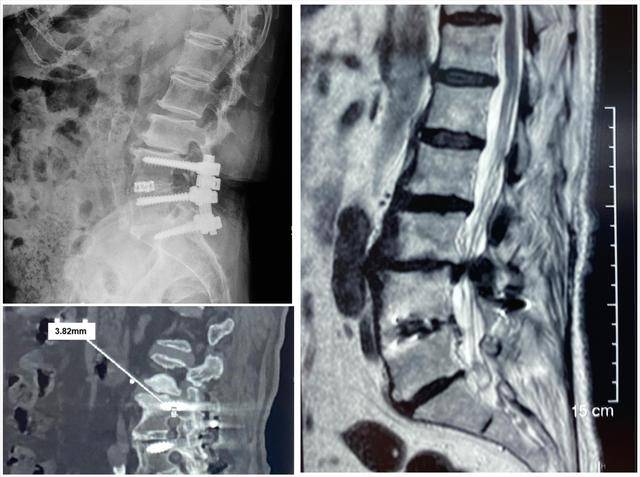

85岁的胡奶奶10年前因腰椎管狭窄症行L4-S1植骨融合内固定术 , 术后症状明显改善 。 近1年内出现腰背部疼痛及双腿麻木症状 , 尤其是买菜、遛弯回家后 , 腰腿疼痛让她很是苦恼 。 反复就诊多家医院 , 均考虑L4-S1手术节段上方应力集中导致L3椎体后滑脱及椎管狭窄所致 , 建议行二次翻修手术治疗 。 鉴于患者高龄 , 常规手术需显露原切口二次手术创伤较大 , 患者于近日前往我院求医 。

【首例|西北首例!O臂结合“天玑”机器人CBT置钉为高龄患者实施腰椎翻修】由于患者高龄且骨质疏松较重 , 在保留原内固定的基础上置入皮质骨轨迹螺钉是微创翻修的首选方案 。 通过术前测量可见双侧椎弓根直径较细且除外原螺钉后仅有不到4mm的空间 , 如何在此“立锥之地”、“矢无虚发”的置入螺钉是翻修手术的难点 。